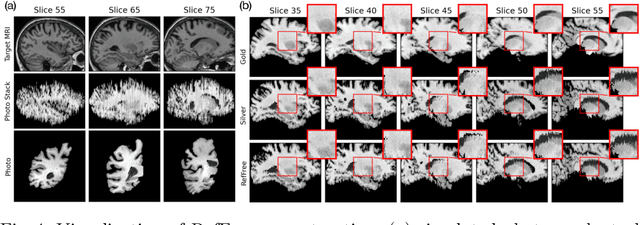

Abstract:Correlation of neuropathology with MRI has the potential to transfer microscopic signatures of pathology to invivo scans. Recently, a classical registration method has been proposed, to build these correlations from 3D reconstructed stacks of dissection photographs, which are routinely taken at brain banks. These photographs bypass the need for exvivo MRI, which is not widely accessible. However, this method requires a full stack of brain slabs and a reference mask (e.g., acquired with a surface scanner), which severely limits the applicability of the technique. Here we propose RefFree, a dissection photograph reconstruction method without external reference. RefFree is a learning approach that estimates the 3D coordinates in the atlas space for every pixel in every photograph; simple least-squares fitting can then be used to compute the 3D reconstruction. As a by-product, RefFree also produces an atlas-based segmentation of the reconstructed stack. RefFree is trained on synthetic photographs generated from digitally sliced 3D MRI data, with randomized appearance for enhanced generalization ability. Experiments on simulated and real data show that RefFree achieves performance comparable to the baseline method without an explicit reference while also enabling reconstruction of partial stacks. Our code is available at https://github.com/lintian-a/reffree.